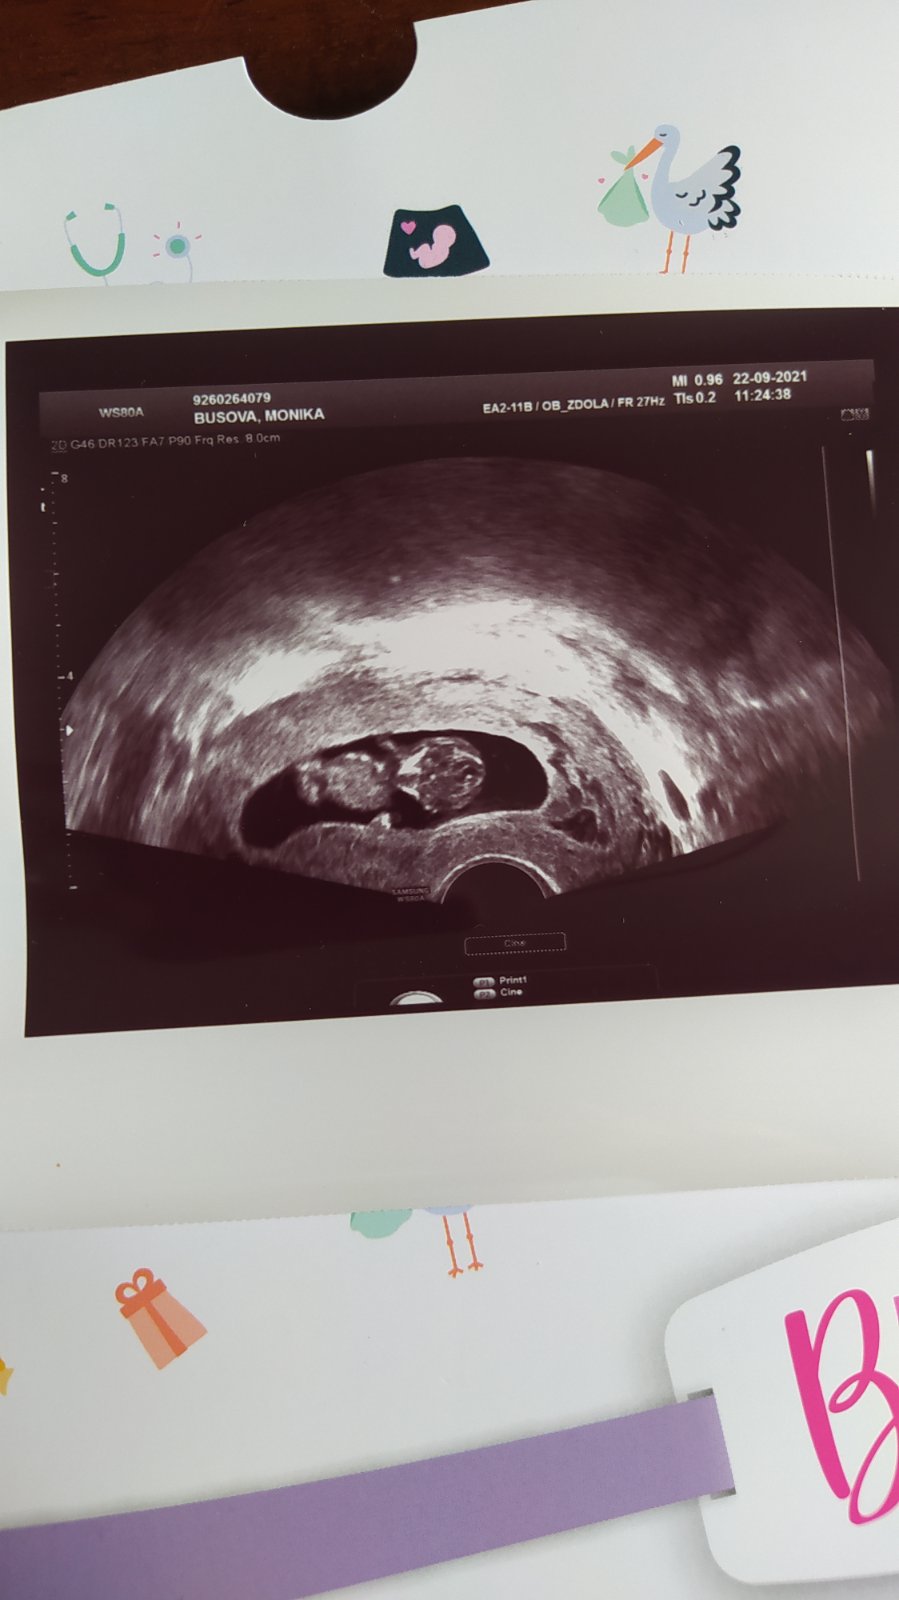

Ahoj, dnes kontrola a miminko roste, jak má 🙂 Zase mám v bříšku akční miminko, trvalo snad 5minu, než ho mohla doktorka změřit 😂